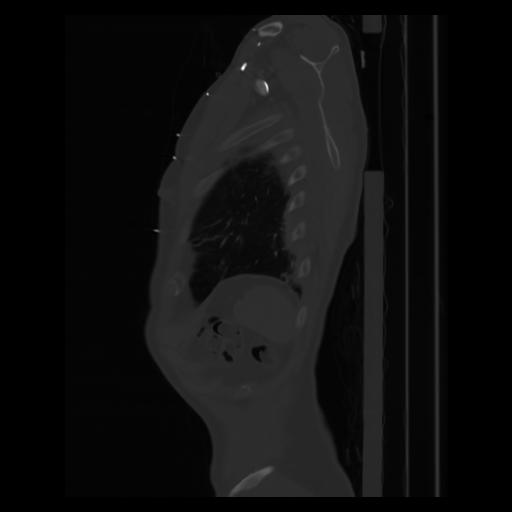

30 CUERPO,CE,Sagittal,3.000,CUERPO,Sagittal,